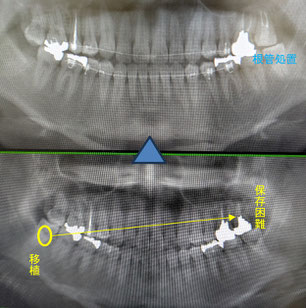

成人の智歯(親知らず)の移植例

病気が大きいため抜歯した所に下顎から親知らずを移植しました。この場合は、歯の神経などを取り除く根管処置が必須となりますが、しっかり処置できていれば全く問題なく移植歯は健全な状況を保ちます。